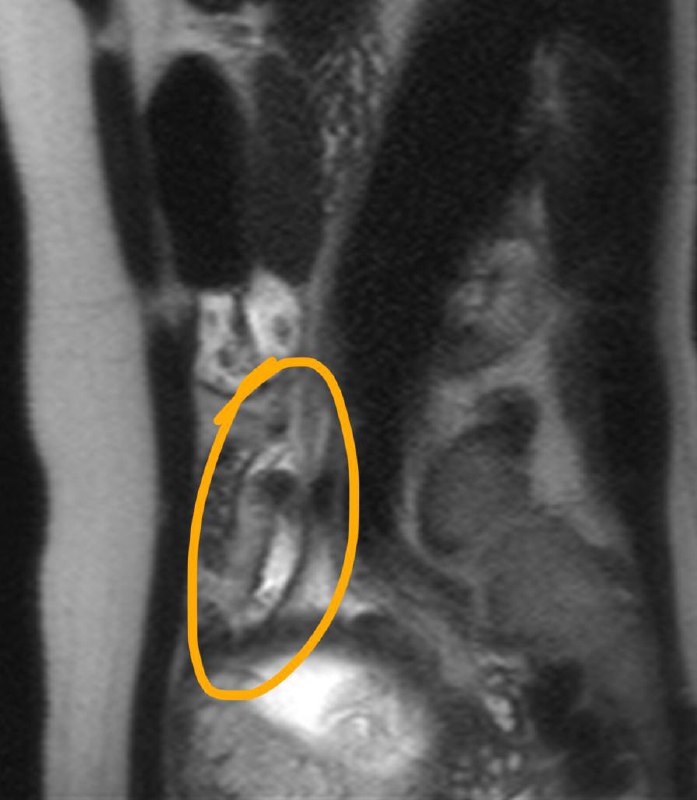

По опыту скажу: когда видишь вот такого, худющего пациента, с таким черным (особенно на Т1, хотя и на Т2, как правило, тоже) костным мозгом, да ещё и со спондилодисцитом, можно не сомневаться, что перед тобой - ВИЧ-инфицированный, и CD4-клеток у него уж точно меньше 150.